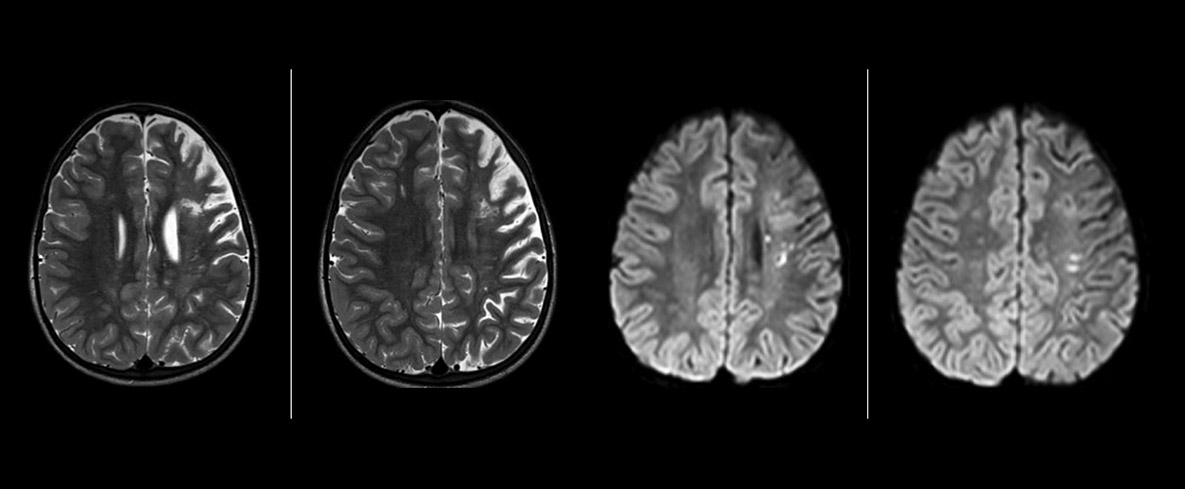

The value of susceptibility weighted imaging in visualizing brain injury is well documented. The Philips multi-echo SWIp technique provides fast susceptibility weighted imaging with enhanced susceptibility contrast and high resolution.

“Pediatric imaging is not without its challenges,” Dr. Miller says. “Since our patients are often very small, we need very high-resolution imaging. In cases of brain injury, we need to obtain information quickly so the treating clinicians can make decisions on care. We rely on high resolution and robust imaging capabilities, and SWIp provides that.”

“SWIp helps us identify blood or blood products, calcification, and diseases that affect the vascular system,” says Dr. Miller. “In children with traumatic brain injuries, it highlights areas that are injured, better than some of the previous techniques that we were using. These children often have micro-injuries that cause small amounts of blood or tissue damage. Adding SWIp helps us to better characterize the extent and nature of the injury. Having characterized an injury to the extent of what’s possible supports our diagnostic confidence.”

“I would definitely recommend other users to implement SWIp. We initially added the SWIp sequence following a lot of support for its utility in the literature. Then we directly compared SWIp to the 2D gradient echo sequences that we were using. After a good amount of clinical experience in seeing its benefits, we were confident to replace the old sequences with SWIp. It gives us a better assessment of the physiological processes of the brain that were less apparent on our previous imaging sequences,” says Dr. Miller. “SWIp is now a routine sequence for imaging traumatic brain injury patients at PCH, and it’s episodically added for patients who have intracranial vascular abnormalities.”

“I believe SWIp is rapidly becoming the standard in imaging traumatic brain injury, because of its high sensitivity to venous blood products. SWIp may even help attract patients; our neurosurgeons often ask to have the patients imaged on our scanners with highly sensitive techniques like SWIp. There’s also a growing application of SWI sequences in other vascular abnormalities because of the possibilities around physiological assessment of the brain than just a standard structural imaging.”